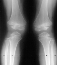

This patient is an 11 year old white male with a diagnosis of Multiple Epiphyseal Dysplasia (MED). Initially he presented with x-rays revealing mild genu valgum which progressed such that he required surgery. He had supracodylar osteotomy which was performed in 1993 for genu valgum . He was last seen in August 1995 for low back pain for which he was prescribed stretching exercises. Since the last visit he has had no problems with his back and denies any complaints in his lower extremities, with the knee valgus remaining stable .

Examination revealed a significantly obese boy in no acute distress. Examination of his back showed no evidence of any curvature. There was no tenderness of his entire spine. Examination of his legs revealed bilateral genu valgum with an intermalleolar distance of 13.5 cm. There was no evidence of any knee effusion or tenderness of the knees. Neurovascular status of the lower extremities was normal with 5/5 muscle tone bilaterally.

In radiograms, the principal findings are the delay and irregularity of ossification of the epiphyses, which are markedly fragmented and mottled. They appear flattened.